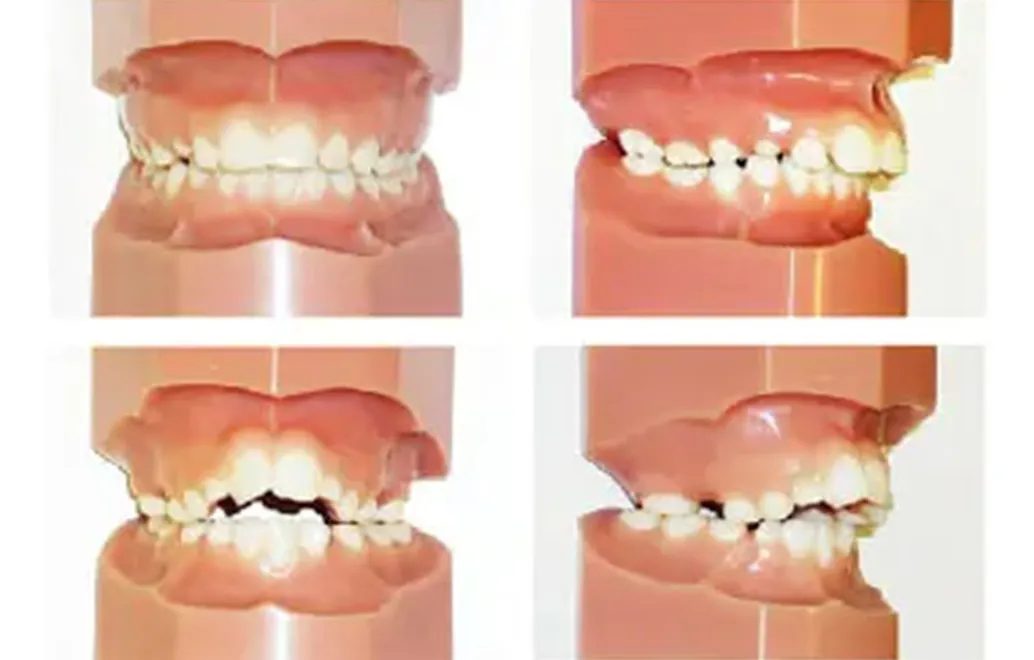

固定式の装置

上顎の拡大装置

上顎の大臼歯にバンドと一体で装着し、歯列を拡大します。

緩徐拡大装置(ミア/クワッドヘリックス/Wアーチ)

下顎の拡大装置

下顎の大臼歯にバンドと一体で装着し、歯列を拡大します。

緩徐拡大装置(バイヘリックス/Wアーチ)